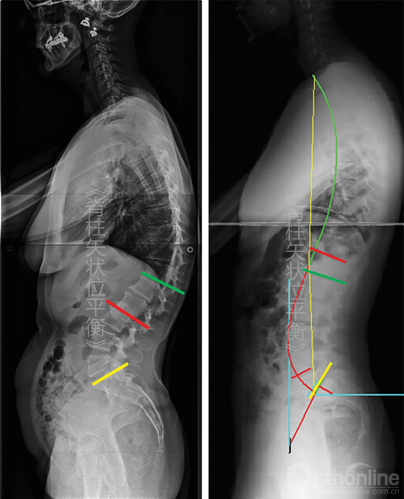

这种功能分段同样可在胸椎应用。脊柱前凸区域与后凸区域之间的关系是上凸区域与后凸区域之间的一种平等关系(图5-9)。

图5-9 根据Berthonnaud等的脊柱分段 CC.颈椎弯曲;SS.骶骨倾斜;TC.胸椎弯曲

由于LL在解剖学和功能上的定义可能存在混淆,所以建议LL描述为T12~L1间隙同骶骨上终板之间的弯曲,而骶骨上终板同拐点之间的弯曲作为脊柱远端前凸(distal spinal lordosis,DSL)(图5-10)。在第一种情况下,定义LL只需要一个角度;第二种情况下,需要一个角度和椎体数量去测量角度(图5-10)。

图5-10对比传统腰椎前凸定义和新的脊柱远端前凸角(DSL)

注意前凸弧的长度,黄线为S1上终板,绿线为L1上终板,红色弧线表示DSL。图示的2种情况下,2个DSL存在显著的生物力学差异(左图DSL较小,右侧较大)

在脊柱颈胸段也同样可以用弯曲顶点进行分段:胸椎后凸则定义为在两个拐点之间的弯曲,颈椎前凸定义为从C3至近端拐点之间的弯曲。因为成像技术(数字影响或EOS系统)已经能清晰的辨认T1椎体,T1椎体上终板的方向便有了更重要的意义。T1倾斜角即为T1上终板同水平线之间的夹角,其对理解颈椎弯曲方向有着重要的意义。

在功能性脊柱分段中,胸椎后凸形态与远端脊柱前凸形态相互影响。首先当胸椎后凸累及椎体长度增加时,远端脊柱前凸形态减小,反之亦然;其次角度方面,胸椎后凸的下弧角等于远端脊柱前凸的上弧角。

由此也引起了一个治疗方面问题,即在手术过程中,当远端腰椎前凸的长度和角度都因上弧角的延长被医源性增大时,胸椎后凸角度也会增加进而引起近端交界性后凸(proximal junctional kyphosis,PJK)。(未完待续)